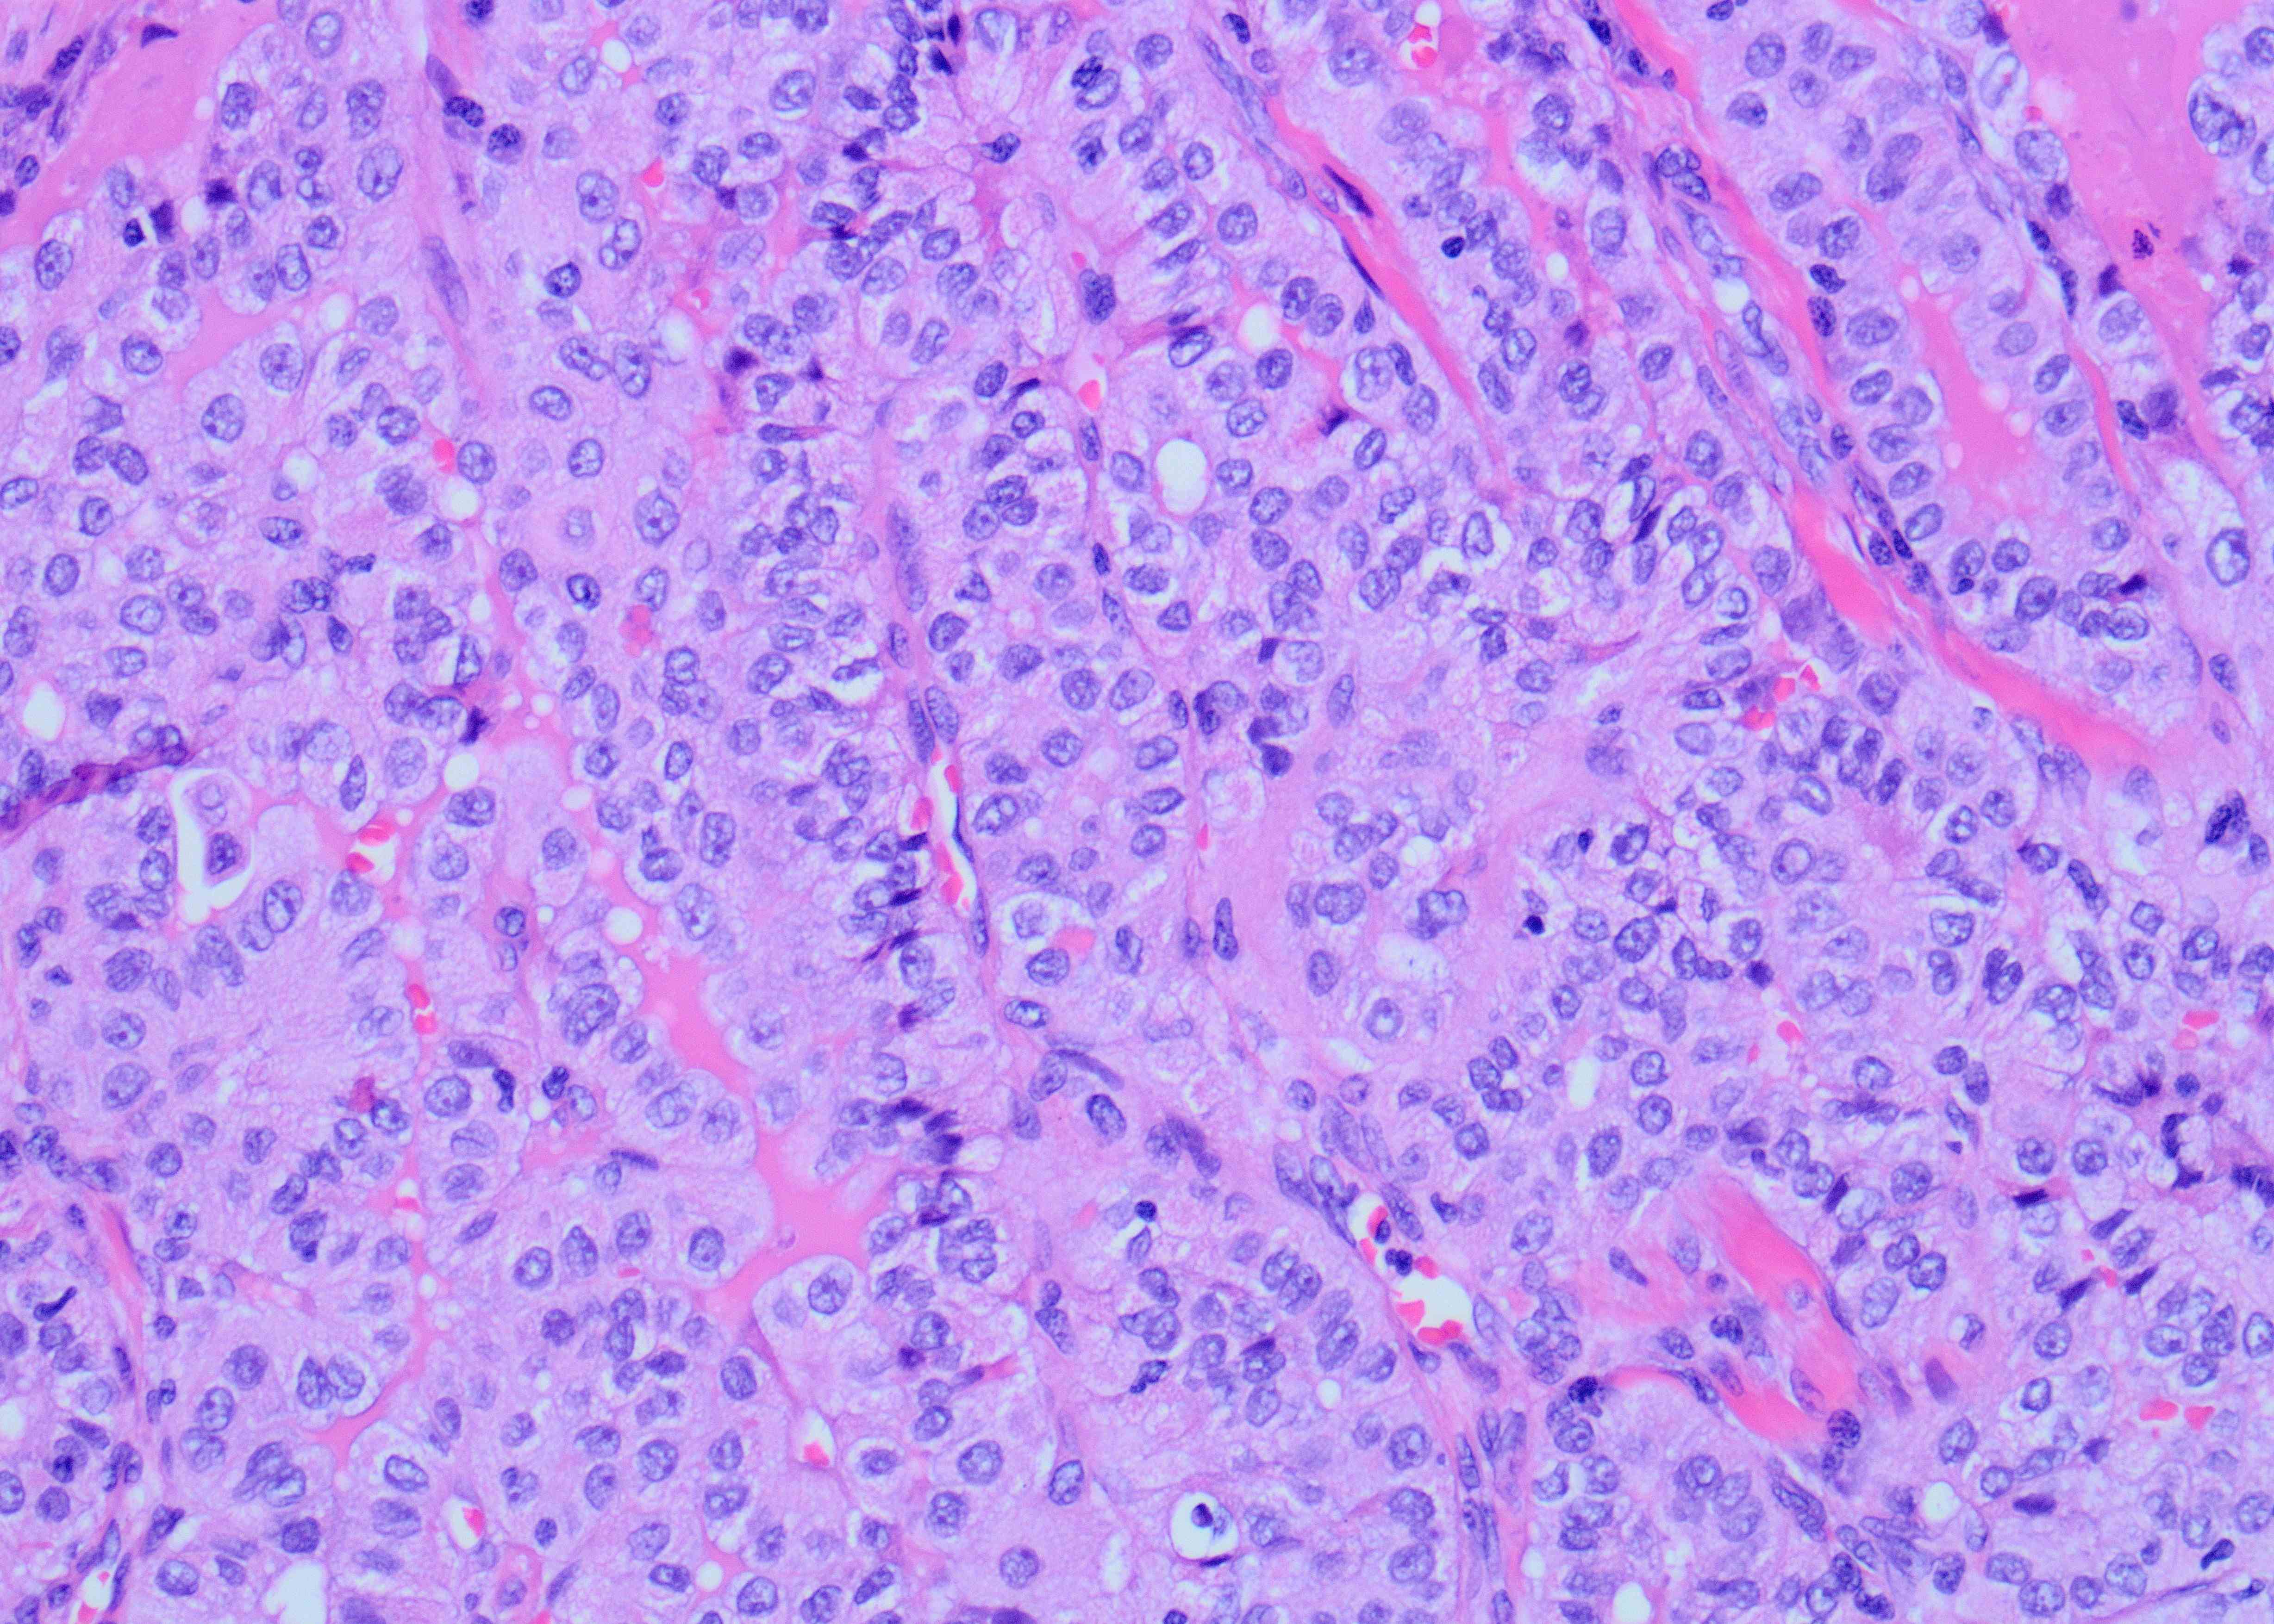

A 45-year old man with a history of PTC, tall cell variant (PT3b N1a M0), s/p total thyroidectomy, central neck lymph node excision and radioactive iodine therapy, presents with new neck mass. Figures a & b show FNA of the mass.

Although the specimen source was described as a neck mass, the presence of scattered lymphocytes in the back ground is suggestive of a lymph node aspirate. In addition, there are scattered clusters of large epithelioid cells but with relatively low nuclear to cytoplasmic ratio due to moderate amount of cytoplasm showing tapered cytoplasmic tails (Figure A). The high power shows a syncytial aggregate of atypical cells (Figure B). These cells have moderately abundant amount of granular cytoplasm with distinct margins. Occasional cells have tall cell morphology, evident predominantly along the periphery of the cluster as well as a single cell with soap bubble like intranuclear pseudoinclusion (arrow). The cytomorphology is identical to the metastatic cells present in the previously excised cervical lymph node (Figure C). All these features favor tall cell variant of papillary thyroid carcinoma (PTC), metastatic possibly to a cervical lymph node. Histopathologic feature of primary PTC, tall cell variant, is shown in Figure D.

PTC is the most common malignancy of the thyroid gland and has overall a favorable prognosis, with few exceptions like PTC, tall cell variant. This variant of PTC is often associated with more aggressive behavior with a higher risk of recurrence than classic PTC. Therefore, a preoperative diagnosis of tall cell variant or even noting the tall cell features on FNA may help in triaging for appropriate patient management. The most helpful cytologic diagnostic features include increased numbers of tall tumor cells arranged as single cells and at the periphery of cellular groups containing granular cytoplasm and distinct cell borders, cytoplasmic tails, and cytoplasmic cuffs (peripheral rimming of cytoplasm in cellular groups). Intranuclear “soap-bubble” pseudoinclusion is not readily identifiable but when present is specific for tall cell variant/ changes.